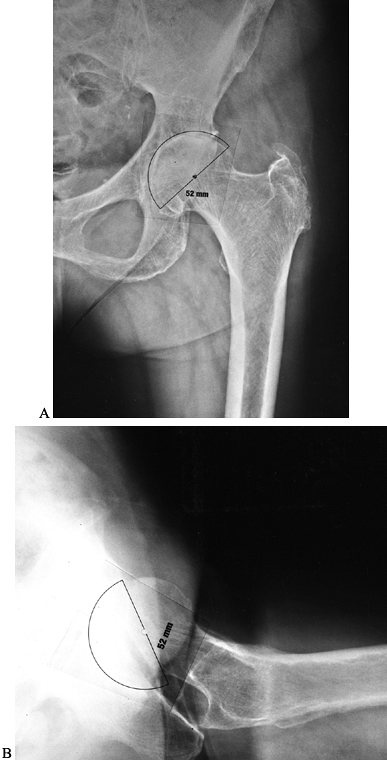

Both the AP and true lateral films of the hip and pelvis help determine

implant size. The goal is to optimize socket orientation and contact

with native bone and to restore the normal hip center of rotation when

possible. The optimal socket position is 40° to 45° of abduction on the

AP radiograph and 10° to 25° of anteversion on the true lateral

radiograph. Most surgeons prefer to target the lower range of

anteversion when an anterolateral approach to the hip is used, and the

higher range when a posterolateral approach is used. Anticipate areas

where bone removal or graft reconstruction will be required. In most

cases of degenerative disease, plan to remove a small amount of medial

bone to place the acetabular prosthesis in an appropriate position,

that is, touching the lateral aspect of the foveal bone

(radiographically, the teardrop). On the AP radiograph, note the amount

of socket left uncovered laterally. On the true lateral radiograph,

note the position of the socket relative to the ischium and anterior

wall of the acetabulum (Fig. 105.6B). Knowing

the expected relationship of the socket to the pelvic landmarks

improves socket positioning during surgery. Finally, mark the socket

center of rotation on preoperative radiographs (Fig. 105.6A).

![]() |

Figure 105.6. A:

AP hip radiograph with acetabular component template in place. The cup is oriented in approximately 40° of abduction. The cup is positioned properly, with the medial socket against the lateral aspect of the radiographic teardrop. From the templating, the surgeon can anticipate the need to deepen the socket slightly by reaming away osteophytes medially so as to position the socket properly. The planned center of hip rotation is marked with a dot. B: True lateral hip radiograph with acetabular component template in place. The cup is oriented in about 20° of anteversion. From templating, the surgeon should expect that the rim of the acetabular component will be inset slightly with respect to the anatomic acetabular rim. |